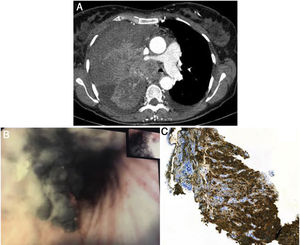

A 54-year-old, non-smoking woman presented with dry cough, asthenia and dyspnea for one month. Six years before, she had a history of left axillary malignant melanoma submitted to surgical treatment with sentinel lymph node biopsy - pathologic staging IB (T2aN0M0). The patient maintained an annual clinical and radiological surveillance, without relapse. On physical examination, she had decreased murmur in the right hemithorax and a palpable right supraclavicular adenopathy. Chest computed tomography showed a massive right upper lobe neoformation with 9cm×12cm (Fig. 1A) with invasion of the right upper lobe bronchus (RULB) and the right pulmonary artery, causing extrinsic compression of the brachiocephalic trunk. Flexible bronchoscopy revealed black pigmented endobronchial lesion, leading to nearly occlusion of the RULB entrance (Fig. 1B). Endobronchial biopsies were compatible with metastatic melanoma (Melan-A and HMB45 expression – Fig. 1C). Due to the progressive brachiocephalic trunk tumoral occlusion, she was referred for emergent palliative radiotherapy, but died shortly thereafter.

A: Chest computed tomography showed right upper lobe mass with 9cm×12cm, with invasion of RULB and the right pulmonary artery. B: Bronchoscopic examination revealed black pigmented endobronchial lesion, leading to partial occlusion of the RULB. C: Immunohistochemical analysis showed Melan-A and HMB45 expression in tumor cells.